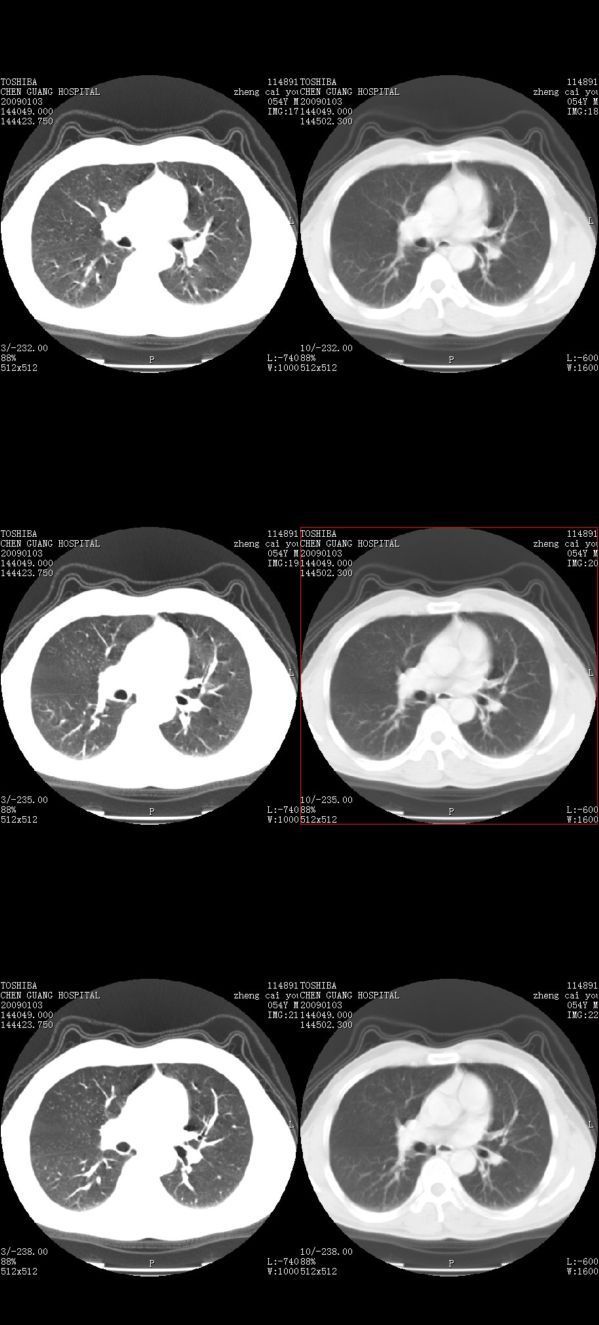

男,54岁,平时有吸烟后咳嗽、咯痰史,因右侧胸部(腋窝下)疼痛来检查平片,见右下肺动脉干起始处处结节,后到同学处做了平扫及增强。请各位老师帮忙看一下,不甚感谢!!!!!

多为血管断面影;建议必要时行ct增强扫描检查。

没有纵膈窗,也没有增强,确实不好说。从连续层面来看像是血管影。不放心做个强化最好了,毕竟是自己最亲的人!!

似乎是血管啊,连续几层都可以看见,希望高手指点迷津!!

肺窗薄扫、常规扫描均未见明确病变;右下肺门圆形与肺血管等密度影,考虑为血管变异;应该要纵隔窗才能进一步明辨。

主要应该看一下纵隔窗,感觉到右肺门的血管有局限性的扩张,呈结节状,再做个增强ct扫描.